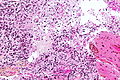

Microscopic

Features:

- Large cell lymphoma.

- Size = 2x diameter normal lymphocyte.

- Nucleolus - common.

- Perivascular clustering.

Images